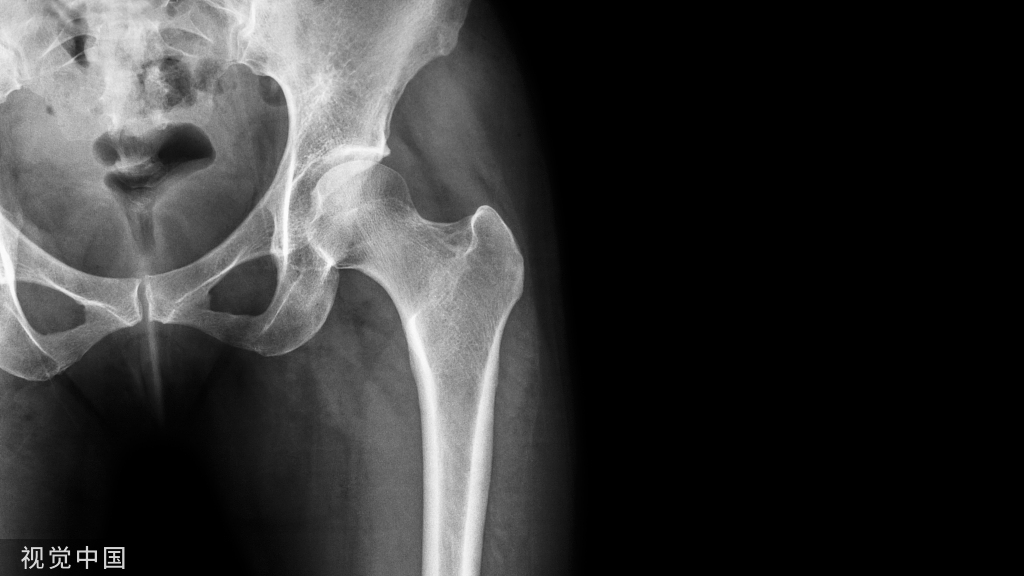

首先,发生断针的第一时间,医生会记录一些数据,包括断针的种类、型号、折断面直径、长度、折断面至标志点的距离。拍片确认根管情况。